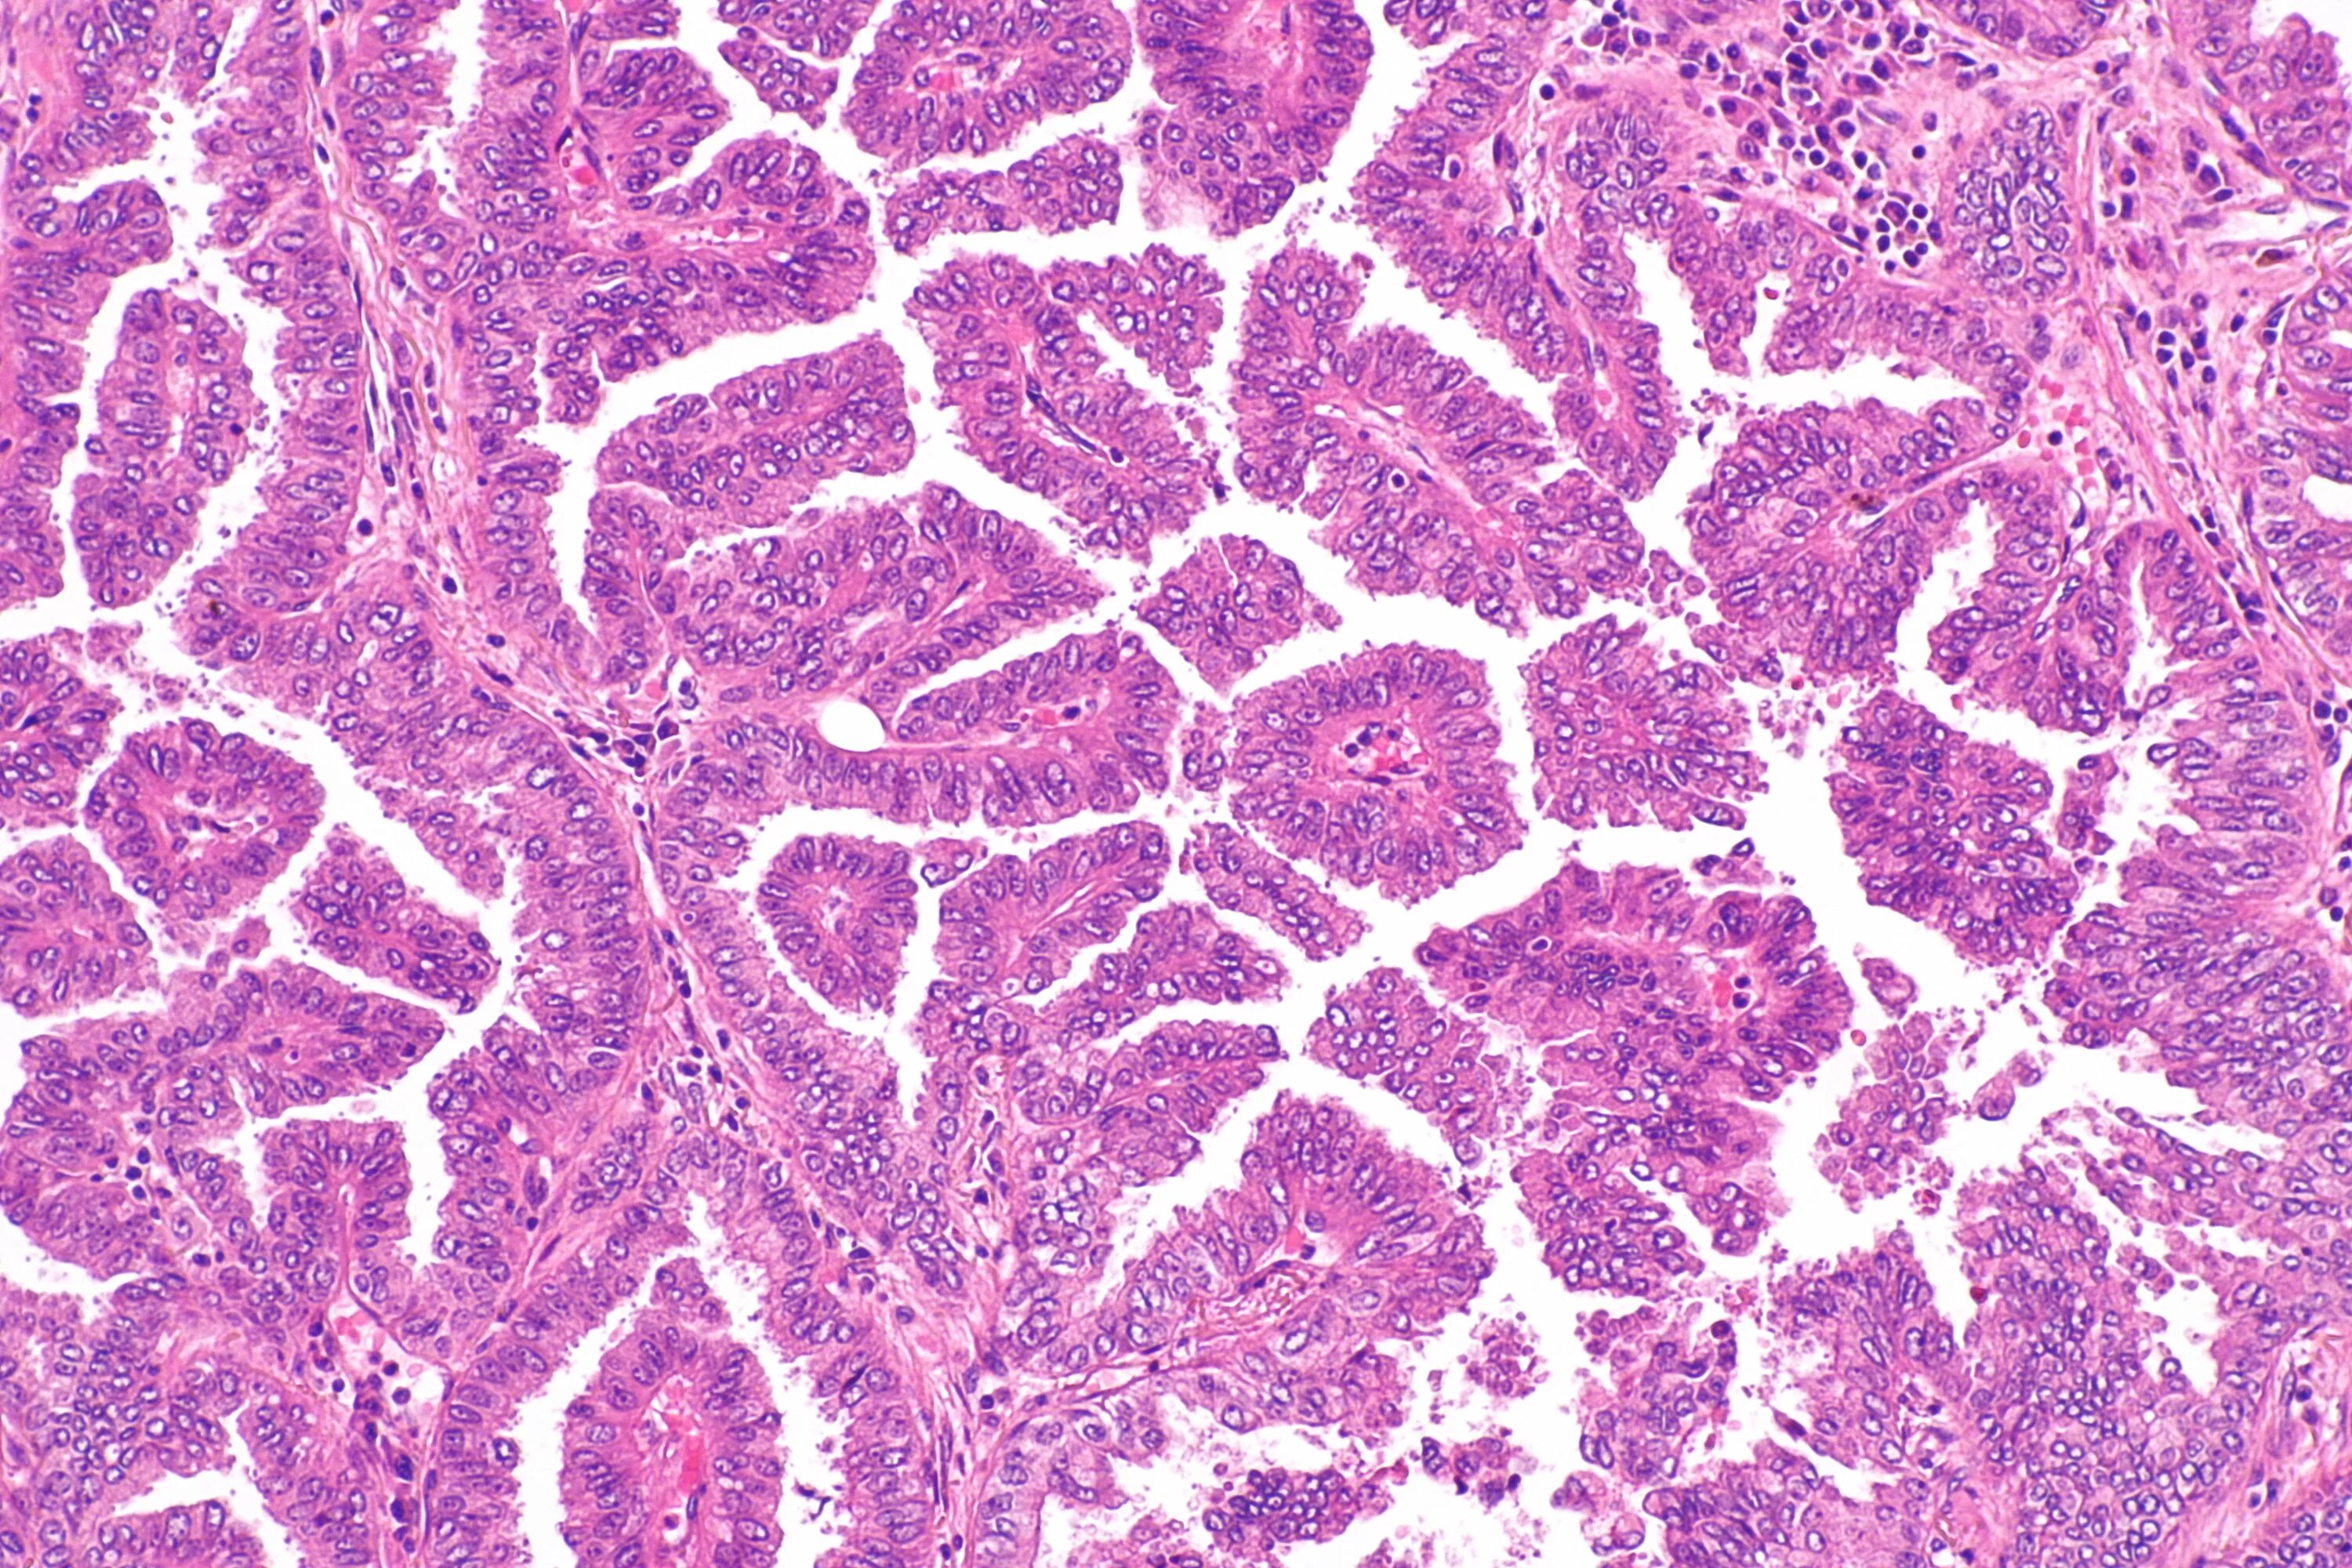

Гистологические варианты